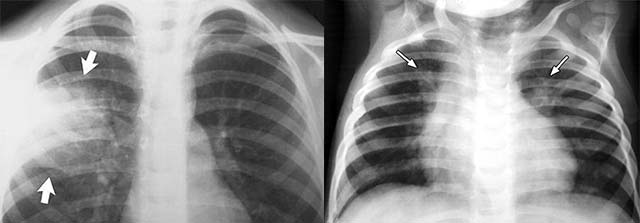

Сделать рентген – на снимке жидкость, скопившаяся в легких, проявится характерным помутнением. К сожалению, этот фотокадр только показывает застойный сгусток, но он практически ничем не отличается от изображений других легочных заболеваний (например, бронхопневмонии), и к тому же не все больницы имеют аппаратуру для обследования лежачих больных.

Вторичная пневмония, вызванная другой болезнью, чаще всего локализуется в нижней доле правого легкого, то есть в самой удаленной от сердца области. Именно здесь и следует ее искать в первую очередь.